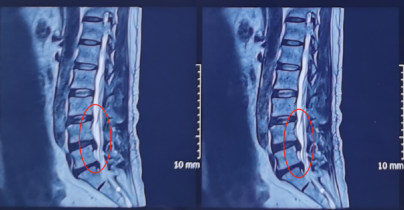

术前影像学资料

在严格执行相关收治程序后,将赵女士收治入院,并为其尽快安排了椎间孔镜手术治疗。手术由熊东主任亲自操作,在内镜下精细操作,成功摘除了突出的椎间盘组织。术后,赵女士的右腿疼痛明显缓解了,第二天就可以下床走路,和术前走路的样子相比判若两人。

陕西冶金医院神经脊柱科的张少华主任、熊东主任接诊后,为小孙进行了详细的查体,并结合各项检查结果和影像学片子,发现他在腰5/骶1节段出现了比较严重的腰椎间盘突出,并造成较为严重的神经受压。